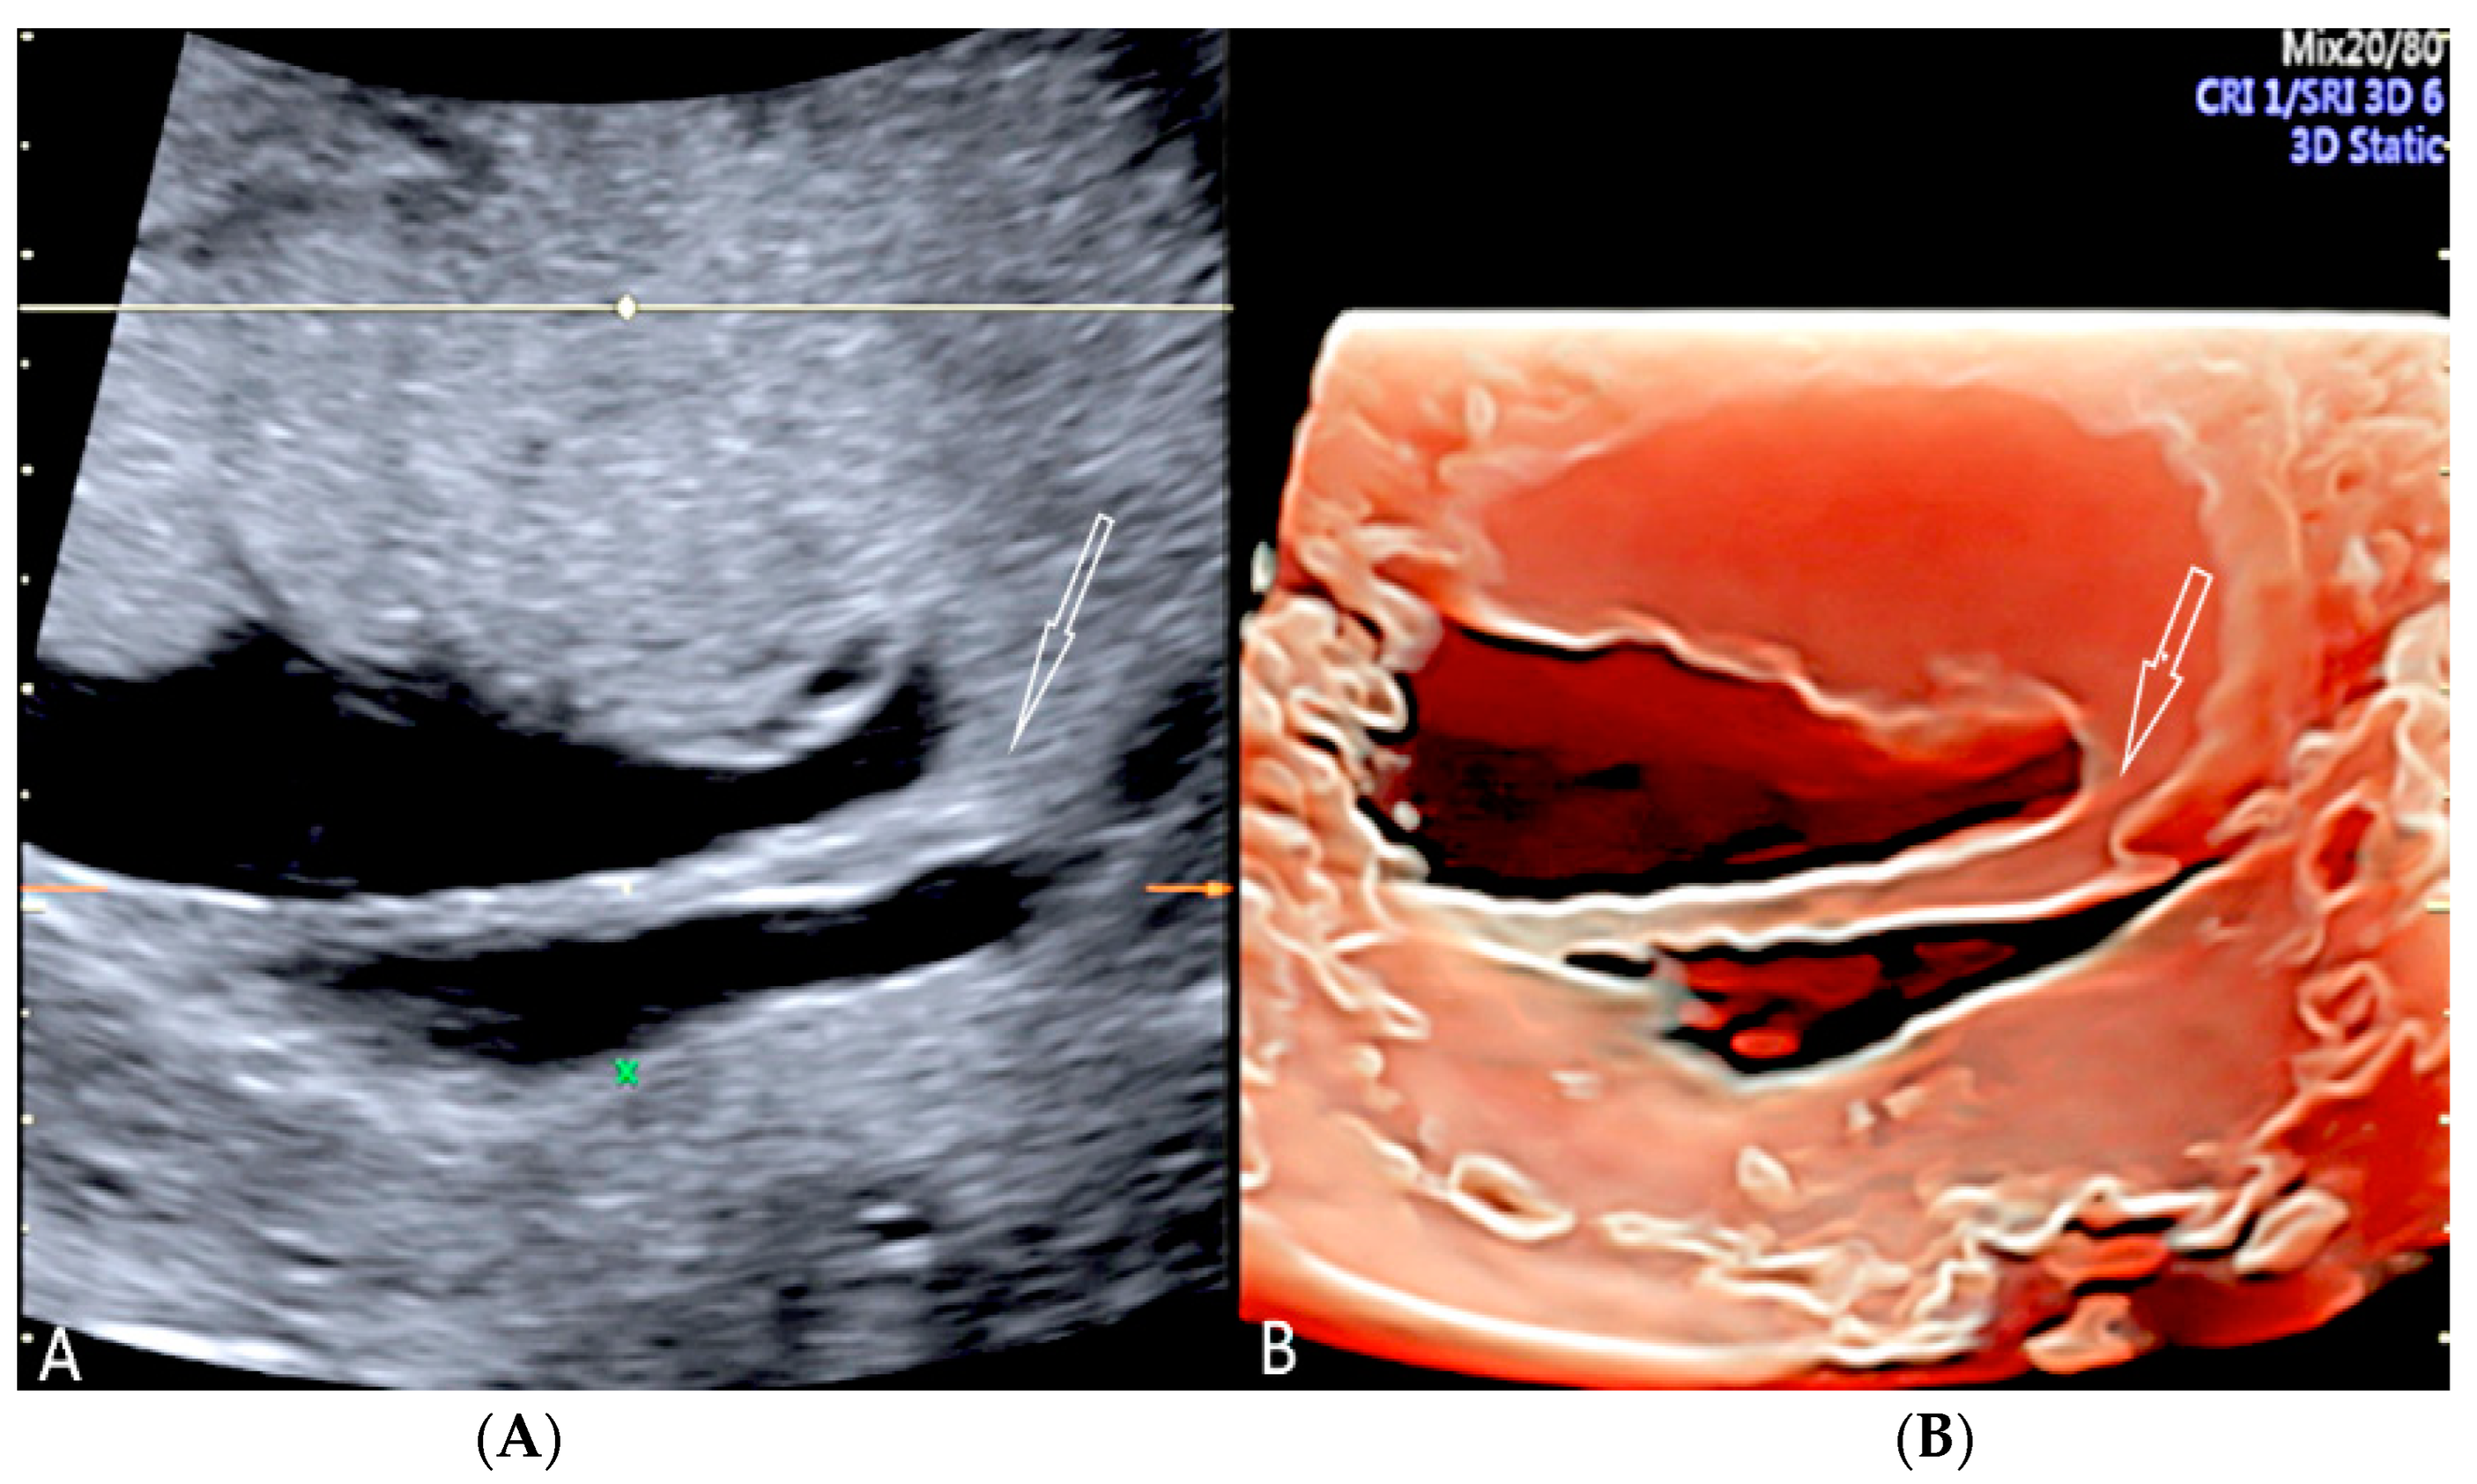

Circumvallate placenta is an abnormality in the area between the placental surfaces, in which the chorionic plate is smaller than the basal plate with protruding peripheral placental tissue [1,32,33]. It is associated with a higher risk of preterm delivery, vaginal bleeding during pregnancy, subchorionic hematoma, preterm premature rupture of membranes, placental insufficiency and placental abruption, especially when maternal serum alpha-fetoprotein is elevated (1.4 MoM) (multiple of the median) and when UtA-PI (uterine artery-pulsatility index) of 1.2 [27,32,33,34]. A sonographic diagnosis can be made during the 18–21 ultrasound week scan, when the average placental thickness is 2.74 ± 0.53 cm [33]. A raised edge of the placenta appearing as an echodense ridge and a circular depression with thick peripheral ring on the chorionic plate has been proposed by Arlicot et al. [35] as the “tire sign” and may be a useful clinical marker of circumvallate placenta when using 3D ultrasound [1,27,36]. (Figure 8, Figure 9 and Figure 10).

Circumvallate placenta with anterior placenta at two-dimensional ultrasound (A). Three-dimensional ultrasound using HD-Live Silhouette™ mode (B) at 20 week’s gestation shows the raised edge of the placenta as a linear band of tissue that may mimic a uterine synaechia (arrows).

(A,B) Circumvallate placenta (pl.) with posterior placenta. Two-dimensional and three-dimensional ultrasound using HD-Live™ mode showing a “shelf-like” structure.